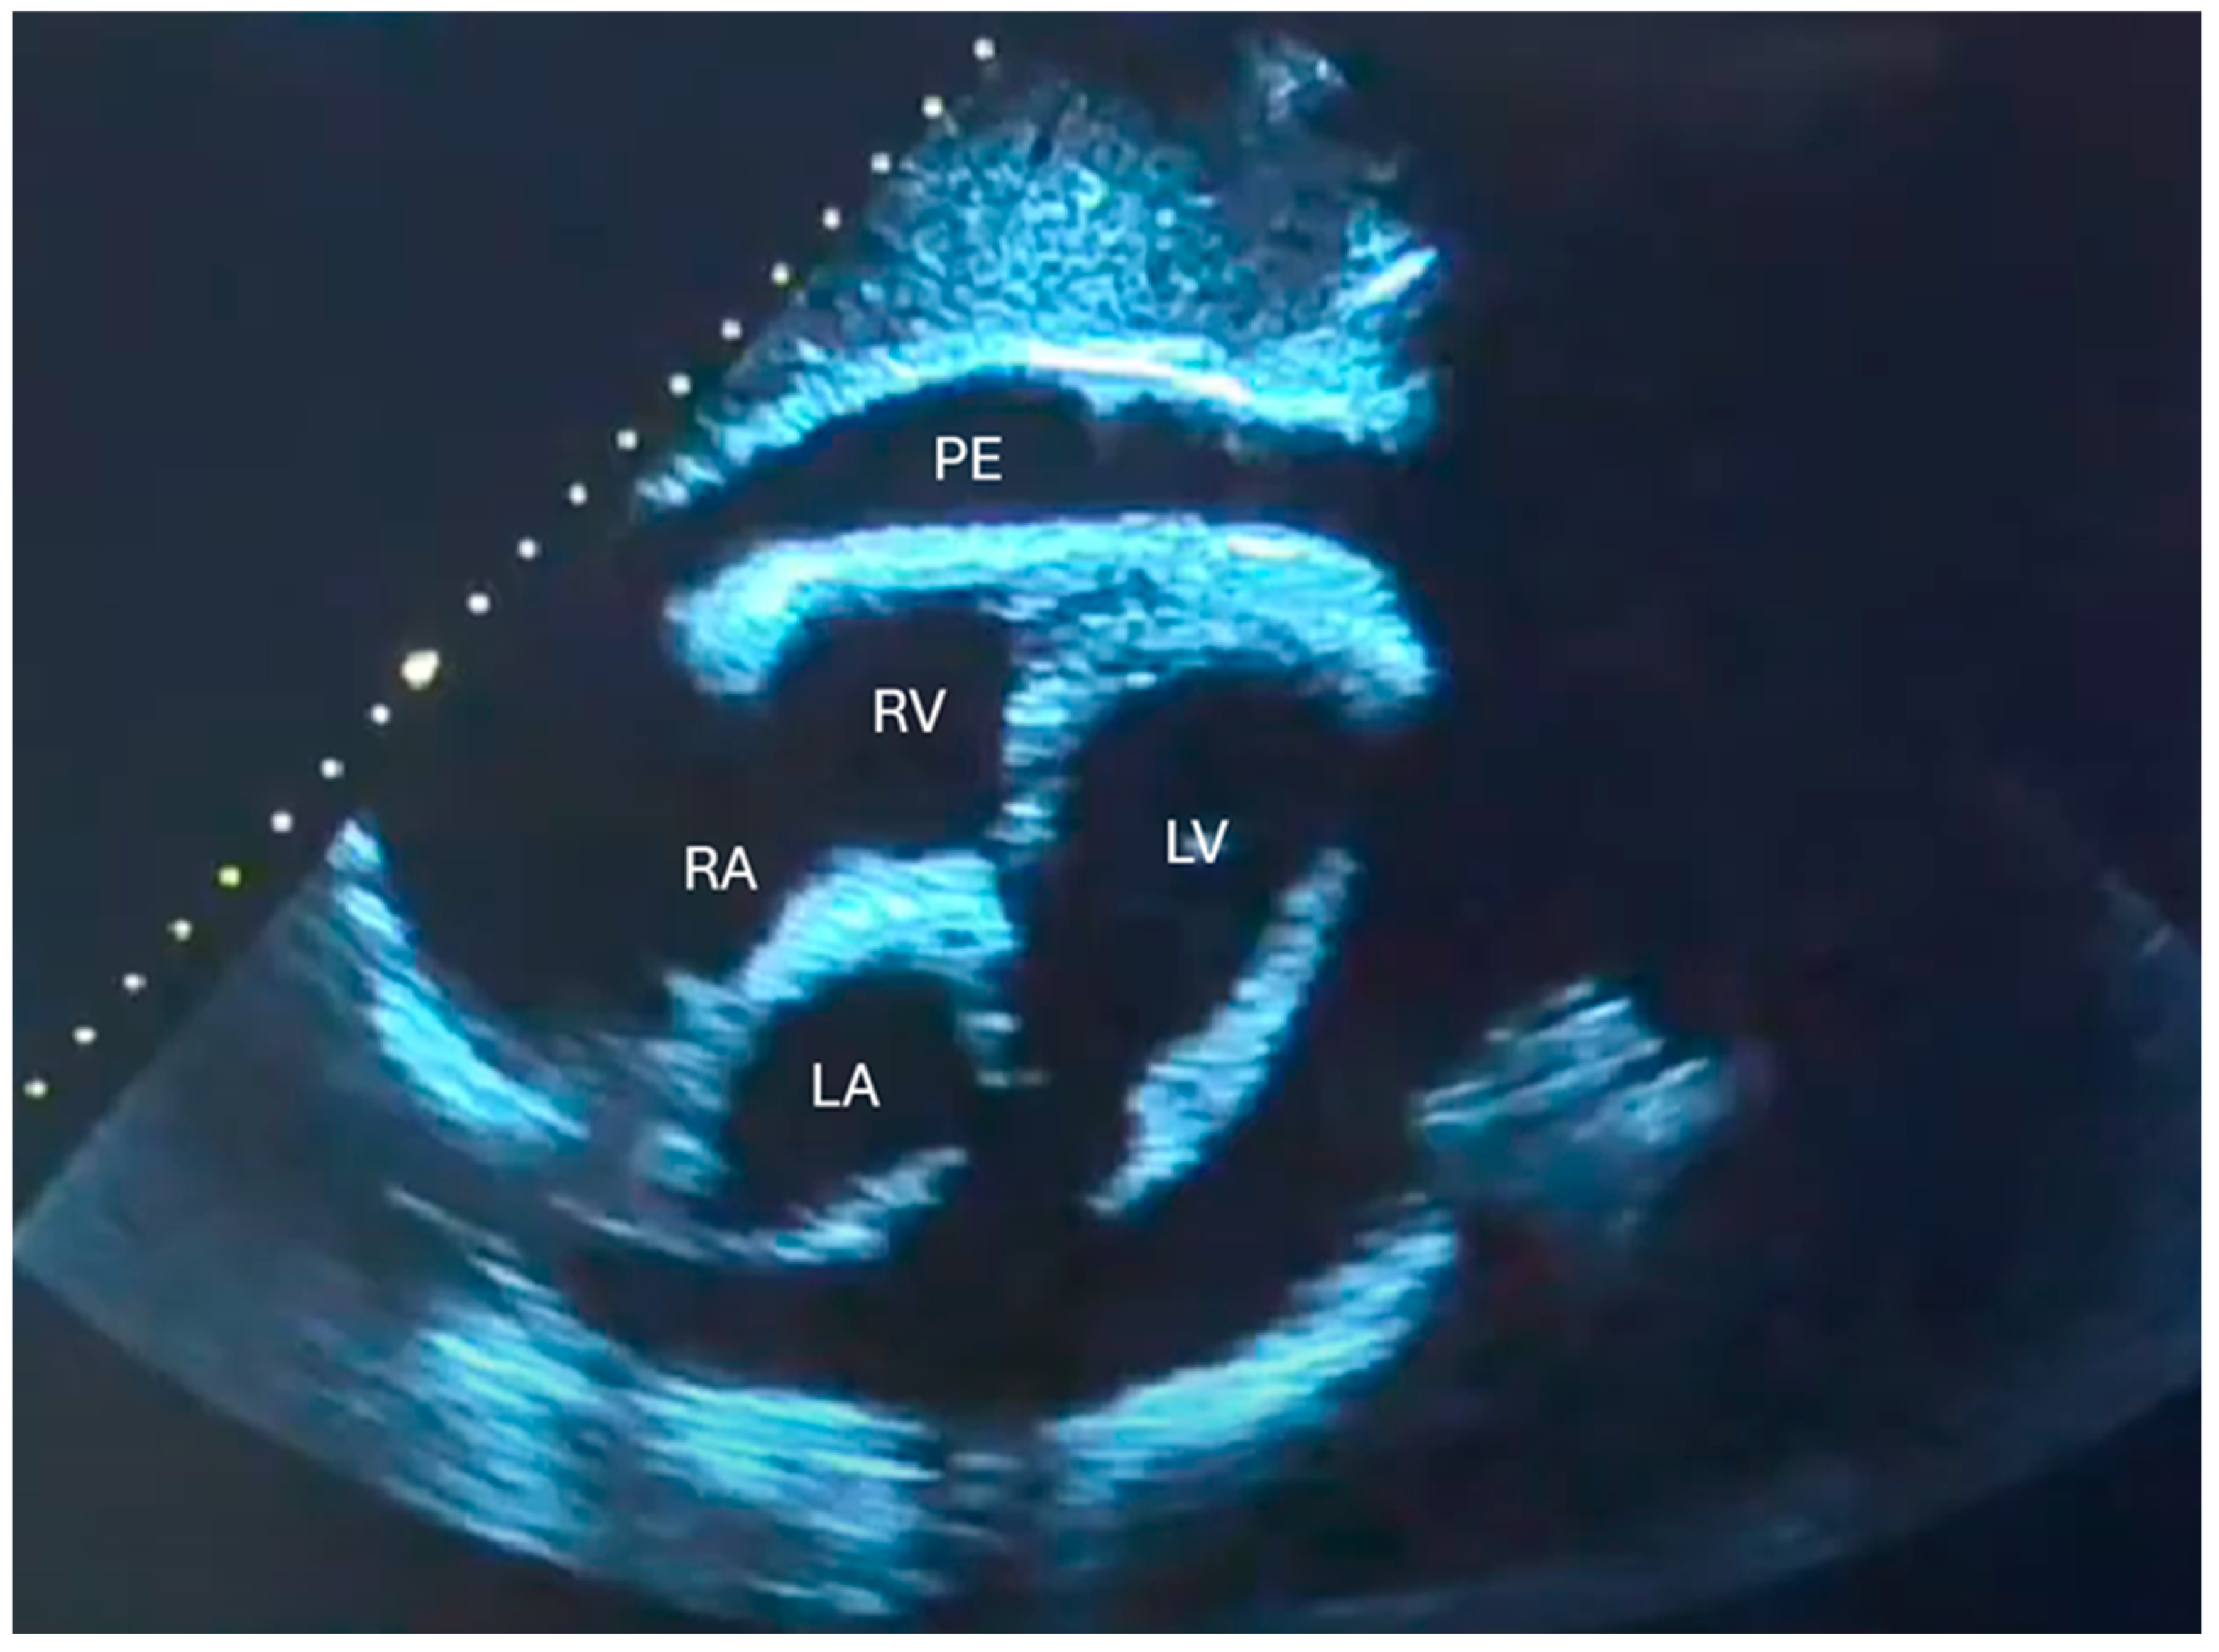

- Is there pericardial effusion or tamponade?

- Tayal, V.S.; Kline, J.A. Emergency echocardiography to detect pericardial effusion in patients in PEA and near-PEA states. Resuscitation 2003, 59, 315–318. [Google Scholar] [CrossRef]

- Kennedy Hall, M.; Coffey, E.C.; Herbst, M.; Liu, R.; Pare, J.R.; Andrew Taylor, R.; Thomas, S.; Moore, C.L. The “5Es” of emergency physician-performed focused cardiac ultrasound: A protocol for rapid identification of effusion, ejection, equality, exit, and entrance. Acad. Emerg. Med. 2015, 22, 583–593. [Google Scholar] [CrossRef]

- Imazio, M.; Mayosi, B.M.; Brucato, A.; Adler, Y. Pericardial effusion triage. Int. J. Cardiol. 2010, 145, 403–404. [Google Scholar] [CrossRef]

| Pericardial effusion—detection | Yes | Yes | Yes |

| Tamponade physiology (RV diastolic collapse, inflow variation) | Limited (signs only) | Yes (qualitative + basic Doppler optional) | Yes (full Doppler assessment) |